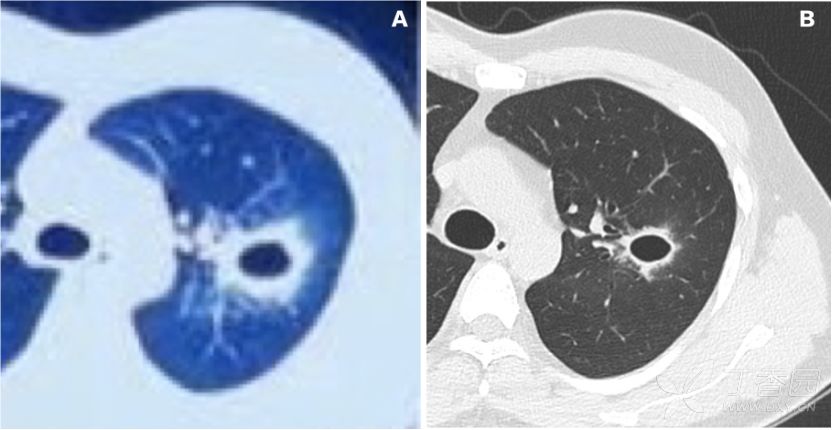

肺脓肿在CT中的典型表现: 空洞大小不一、空洞可单发也可多发、空洞边缘光滑,合并感染时壁增厚而边缘模糊、可见中等或大量脓液。